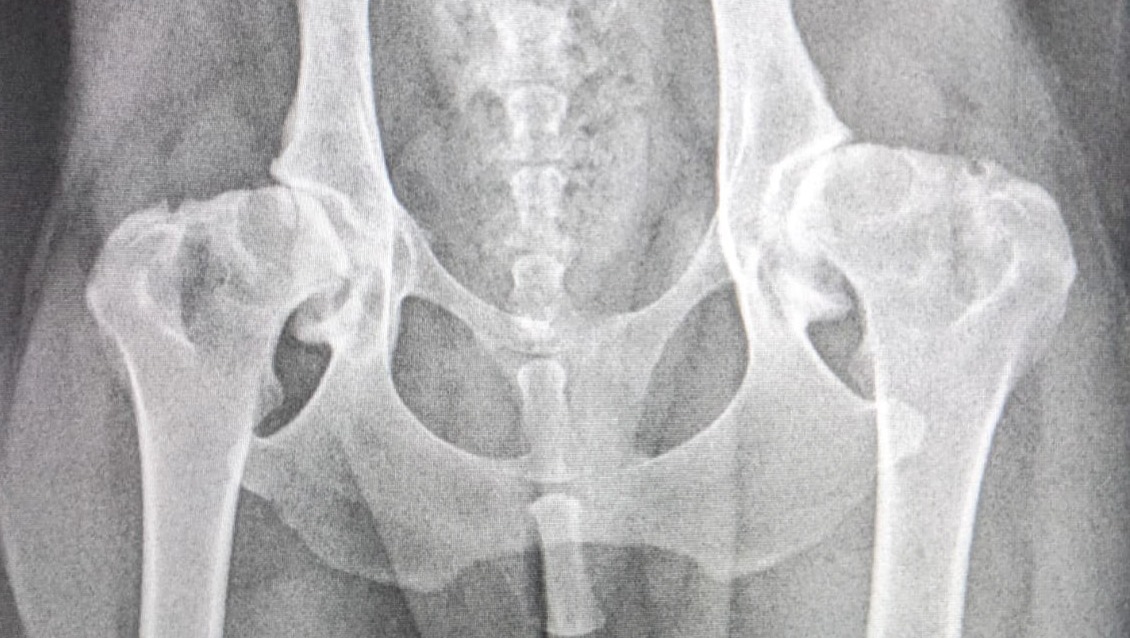

We've just had the results back, from the biopsies, and thankfully they show no signs of cancer, but as you can see from the photo

her hips are horrendous, really bad hip dysplasia, huge arthritic changes and remodeling. I can't begin to imagine how much pain she has been in for most, if not all, of her life.